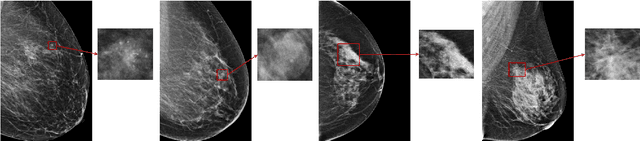

Abstract:Breast cancer is the most common cancer in women, and hundreds of thousands of unnecessary biopsies are done around the world at a tremendous cost. It is crucial to reduce the rate of biopsies that turn out to be benign tissue. In this study, we build deep neural networks (DNNs) to classify biopsied lesions as being either malignant or benign, with the goal of using these networks as second readers serving radiologists to further reduce the number of false positive findings. We enhance the performance of DNNs that are trained to learn from small image patches by integrating global context provided in the form of saliency maps learned from the entire image into their reasoning, similar to how radiologists consider global context when evaluating areas of interest. Our experiments are conducted on a dataset of 229,426 screening mammography exams from 141,473 patients. We achieve an AUC of 0.8 on a test set consisting of 464 benign and 136 malignant lesions.

Abstract:We present a deep convolutional neural network for breast cancer screening exam classification, trained and evaluated on over 200,000 exams (over 1,000,000 images). Our network achieves an AUC of 0.895 in predicting whether there is a cancer in the breast, when tested on the screening population. We attribute the high accuracy of our model to a two-stage training procedure, which allows us to use a very high-capacity patch-level network to learn from pixel-level labels alongside a network learning from macroscopic breast-level labels. To validate our model, we conducted a reader study with 14 readers, each reading 720 screening mammogram exams, and find our model to be as accurate as experienced radiologists when presented with the same data. Finally, we show that a hybrid model, averaging probability of malignancy predicted by a radiologist with a prediction of our neural network, is more accurate than either of the two separately. To better understand our results, we conduct a thorough analysis of our network's performance on different subpopulations of the screening population, model design, training procedure, errors, and properties of its internal representations.